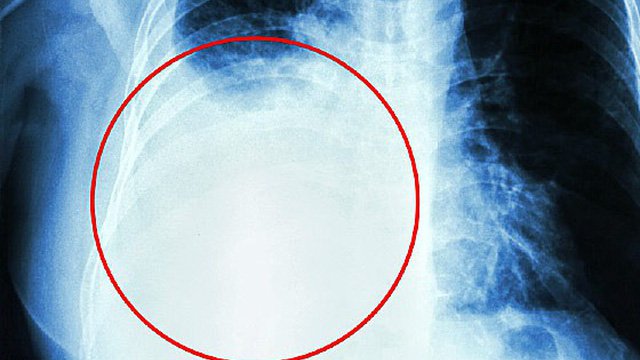

Phổi

Ung thư vú có thể lây lan đến nhiều bộ phận khác nhau trong cơ thể, bao gồm phổi. Tuy nhiên, việc lây lan của ung thư vú đến phổi không phải là điều phổ biến.Khi ung thư vú lây lan đến phổi, nó thường được gọi là ung thư vú di căn đến phổi.

Các tế bào ung thư từ vú có thể lây lan đến phổi thông qua hệ thống mạch máu và mạch lymph. Khi các tế bào ung thư này đến phổi, chúng có thể tạo thành các khối u mới trong phổi.Tuy nhiên, việc ung thư vú lây lan đến phổi không phải là điều xảy ra thường xuyên. Theo các nghiên cứu, khoảng 1-5% trường hợp ung thư vú di căn sẽ lây lan đến phổi.

Thay vào đó, các bộ phận khác như xương, gan và não thường là nơi ung thư vú di căn phổ biến hơn.Việc lây lan của ung thư vú đến phổi có thể gây ra các triệu chứng như khó thở, ho, đau ngực và khó khăn trong việc thở.